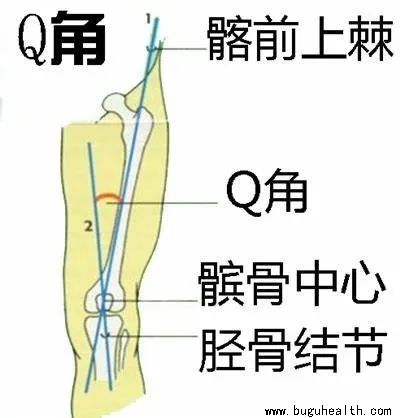

- 有文章提及,髌骨软化症是膝关节损伤中的常见软组织损伤疾病,其发病率在2743名普通人群中高达36.2%。该病以膝关节疼痛为主,以爬楼梯和下蹲痛的临床表现最为显著,对患者日常工作和生活带来严重干扰。尤其是在30-40岁年龄段是髌骨软化症高发年龄,在此年龄段膝关节软骨已开始退变,而此时工作和日常生活也是.....

- 膝关节屈伸活动时膝盖后方的疼痛,在上下楼、下蹲、爬山、搬重物尤为明显,或者用手按压髌骨摩擦推动,感觉到关节里面“沙沙”响,那您就要考虑您是否出现了“髌骨软化”的问题了。膝关节的髌软骨软化症是一种发生在膝关节的髌骨软骨面的退行性改变(俗称的老化),是髌股关节软骨长期慢性磨损引起的。关节软骨会产生软化、.....